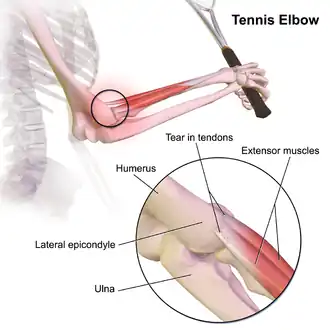

Tennis elbow, also known as lateral epicondylitis, is an enthesopathy (attachment point disease) of the origin of the extensor carpi radialis brevis on the lateral epicondyle.[1][5] It causes pain and tenderness over the bony part of the lateral epicondyle. Symptoms range from mild tenderness to severe, persistent pain.[1][6][7] The pain may also extend into the back of the forearm.[3] It usually has a gradual onset, but it can seem sudden and be misinterpreted as an injury.[8][3][9]

Patients typically feel pain or burning around the outer part of the elbow (lateral epicondyle of the humerus), which can move down the forearm and sometimes up to the upper arm.[10] The pain is worsened by activities that involve wrist extension, such as gripping objects.[14][15] Pain intensity varies from mild to severe and can be intermittent or constant, significantly impacting daily life. Patients also commonly report grip weakness and difficulty lifting.[16]

The extensor carpi radialis brevis is the most commonly affected muscle in lateral epicondylitis (LE), along with other extensor carpal muscles.[15] Due to its unique origin, the ECRB tendon is prone to abrasion during elbow movements, leading to repetitive microtrauma.

Lateral epicondylitis was initially considered an inflammatory process, however there is no evidence of inflammation or repair.[26] Therefore, the disorder is more appropriately referred to as tendinosis or tendinopopathy.[19] Tendinosis, a degenerative condition with fibroblasts, abnormal collagen, and increased blood vessels. Repetitive stress causes microtears, scar tissue formation, and biomechanical changes, worsening symptoms over time.